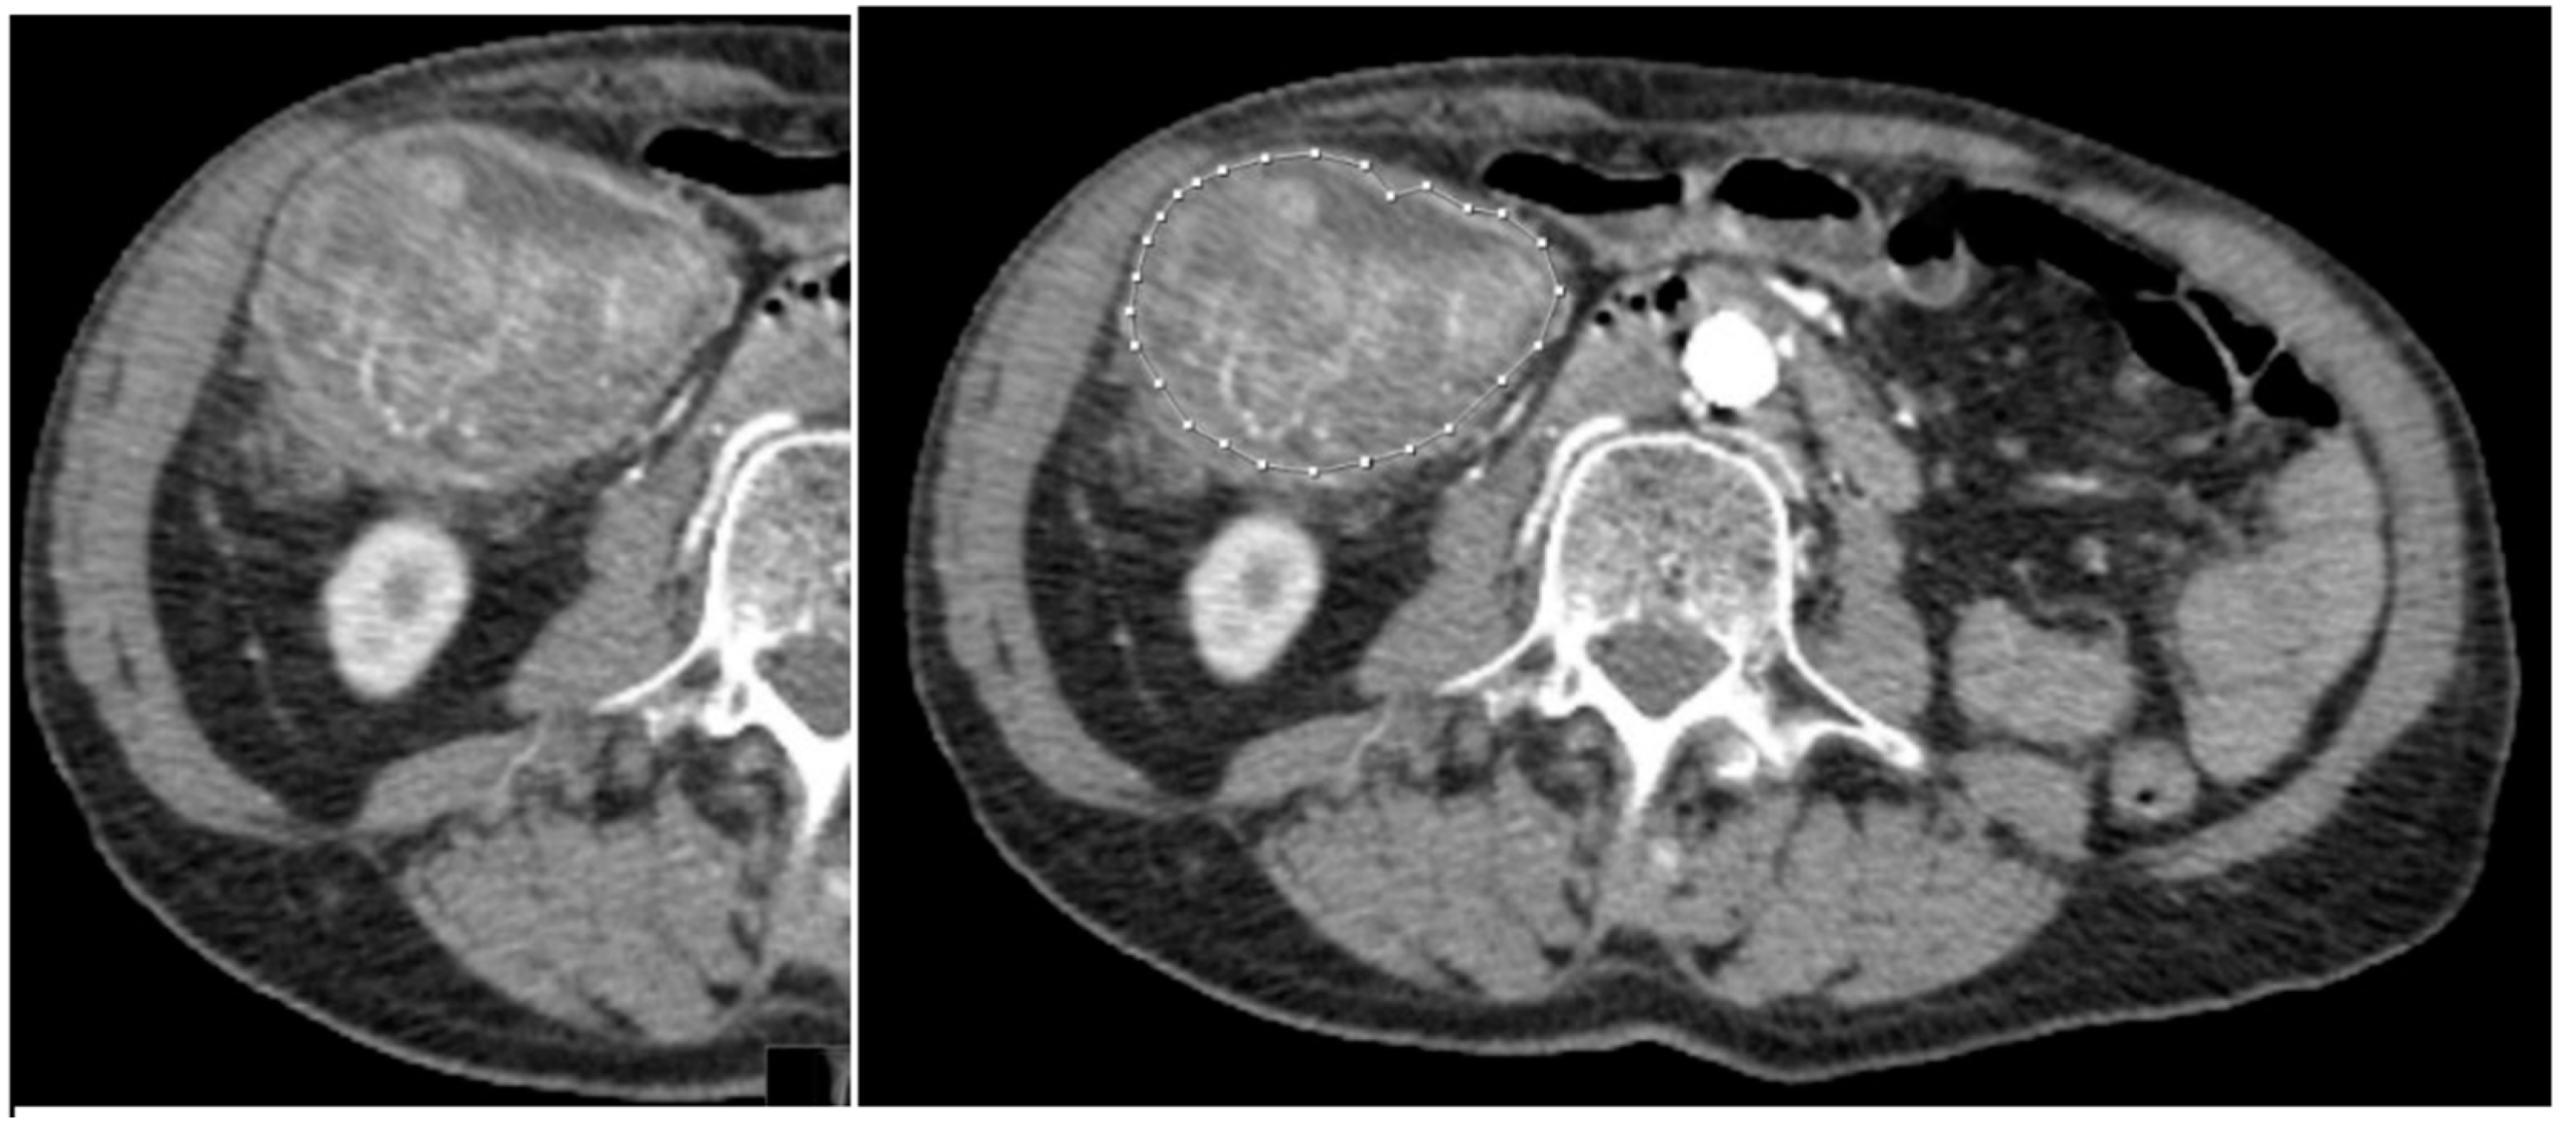

Figure 3. a) Manually segmented non-mutated KRAS tumour. b) Abdominal contrast-enhancement CT of the same patient.